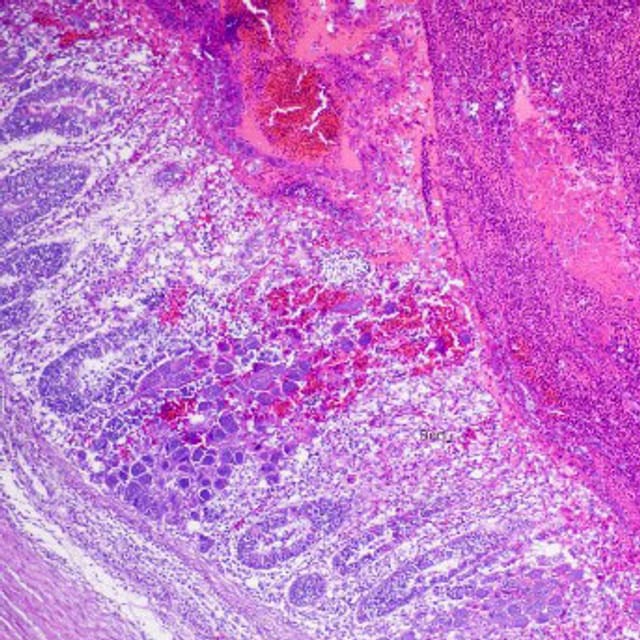

Enhancing Gut Integrity

To address the challenges associated with coccidiosis, the potential of antimicrobial lipids, such as fatty acids and monoglycerides, as antibacterial agents can be considered. These compounds show promise by destabilizing bacterial cell membranes, resulting in a broad spectrum of direct and indirect inhibitory effects[4].

Monoglycerides of short and medium chain fatty acids, such as butyric acid (C4), caprylic acid (C8), caproic acid (C10), and lauric acid (C12), potentially providing systemic and broad-spectrum activity in the gut, aiming to contribute to a reduction in disease incidence, thereby aiming to indirectly minimize costs associated with veterinary interventions. Effective management of pathogen pressure is highlighted as a potential key benefit that can help promote the overall well-being of the poultry flock.

To actively support the balance of the gastrointestinal microflora, a combination of probiotics and prebiotics is beneficial. Bacillus velezensis (formerly B. subtilis) has gained widespread popularity as a probiotic for poultry, known for its multiple beneficial effects ranging from improved gut barrier integrity, mucosal immunity, digestive enzyme activities, and nutrient metabolism[5].

When combined with prebiotics, such as yeast, it creates an environment that promotes the growth and activity of these beneficial microorganisms and enhances the competitive exclusion of pathogens for adhesion sites. This symbiotic relationship, in turn, positively impacts the gastro-intestinal-tract (GIT) by promoting a balanced microflora, strengthening the intestinal barrier and enhancing nutrient absorption. This optimization of the GIT is designed to potentially support improvements in digestion and nutrient absorption, in line with desired poultry health outcomes.